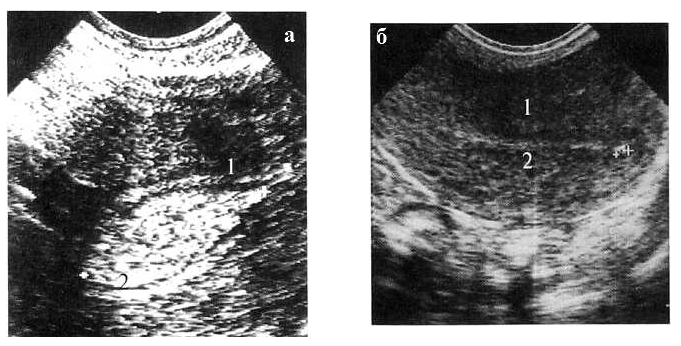

Рис. 2. Больная С. 35 лет. 13 день МЦ.

ЛУГ в эндометрии в дне полости матки. Продольное ТВ-сканирование. 1 — матка, 2 — М-эхо с ЛУГ (УЗ картина напоминает одиночный полип эндометрия)

Этот признак прослеживался как в 1-ю, так и во 2-ю фазы МЦ (рис. За) у всех 232 женщин. Форма ЛУГ была правильная: округлая или овальная, структура — однородной, без наличия кровотока как в центре, так и по его периферии. При исследовании на 4-6 день МЦ (рис. 3б) отмечалось значительное уменьшение образования до 0,6—0,2 см (по длиннику) и до 0,3—0,2 см (по поперечнику). Однако к 8-10 дню МЦ образование в эндометрии имело ту же форму и размеры и практически не менялось до наступления следующей менструации.

Рис. 3а-б.

Рис. 3а. Больная А. 39 лет. 22 день МЦ.

Большой ЛУГ в эндометрии в середине полости матки. Продольное ТВ-сканирование. 1 — матка, 2 — М-эхо с ЛУГ, находящегося в центре полости матки (УЗ картина напоминает большой одиночный полип эндометрия)

Рис. 3б. 5 день МЦ.

Маленький ЛУГ в эндометрии в дне полости матки. Продольное ТВ-сканирование. 1 — матка, 2 — М-эхо с мелким до 3 мм в диаметре ЛУГ